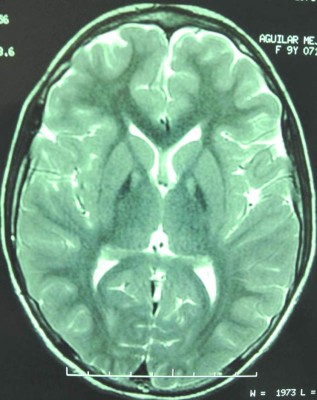

Francelia Mejía posa para el lente de EL HERALDO junto a su sobrina Daniela y su hija Sabini Nicol Aguilar. 6 Sabini lucha contra un enemigo desconocido